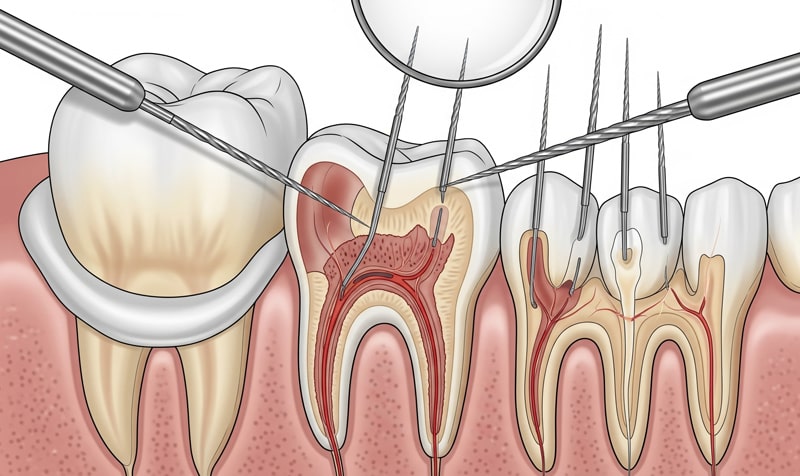

• عکسبرداری و رادیوگرافی از دندان

برای تشخیص میزان و سطح آسیب و همچنین تعیین روش مناسب جهت درمان ریشه دندان، متخصص درخواست عکسبرداری و رادیوگرافی دندان را می دهد.

• تخلیه پالپ عفونی شده

زمانی که ریشه دندان ظاهر شد، امکان دسترسی دندانپزشک به پالپ عفونی شده وجود دارد و به طور کامل کانال ریشه دندان را از آن تخلیه می کند. توجه به این نکته ضروری است که عروق عصبی پالپ به طور کامل قطع شوند، تا در آینده باعث مشکل و درد برای فرد نشوند.

• تمیز کردن کانال ریشه

زمانی که پالپ به طور کامل خارج شد، باید کانال های ریشه به طور کامل تمیز شوند و برای پر کردن آماده شوند. برای اینکه بصورت کامل کانال تمیز شود با محلول های ویژه، آن را شستشو می دهند. این محلول هم عفونت های باقی مانده را برطرف می کند و هم عاملی برای مقابله با میکروب می باشد.

• پرکردن ریشه دندان

حالا که کانال های ریشه به طور کامل پاکسازی شده اند، دندانپزشک با استفاده از ماده گوتاپرکا، اقدام به پر کردن ریشه دندان می نماید. در نهایت یک پانسمان موقت روی دندان قرار می دهد.